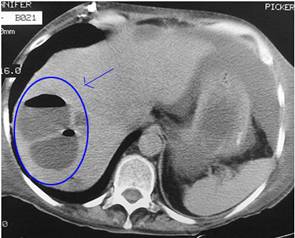

Do đó, liên quan đến câu hỏi của bạn, chúng tôi khuyên bạn nên đưa bạn gái đến một cơ sở y tế khám và đánh giá khối thương tổn (nếu có) trên siêu âm, điều này rất tốt cho bệnh nhân vì sẽ đánh giá tiên tượng điều trị khối thượng tổn có lớn hay nhỏ, có dịch hay không, có nguy cơ vỡ ngoài bao gan hay không?...để mà điều trị cho chính xác.

Cũng nhắc cho bạn biết rằng bệnh sán lá gan lớn là một bệnh lành tính, chữa khỏi hoàn toàn, dùng thuốc đặc hiệu liều duy nhất, tác dụng ngoại ý của thuốc không đáng kể, chưa thấy báo cáo nào cho là nghiêm trọng do thuốc cả. Song cũng không nên cho là lành tính mà không điều trị, sẽ có thể dẫn đến một số biến chứng nguy hiểm (chẳng hạn vỡ ổ abces gây viêm phúc mạc, nhiễm trùng huyết) đến tính mạng bệnh nhân.